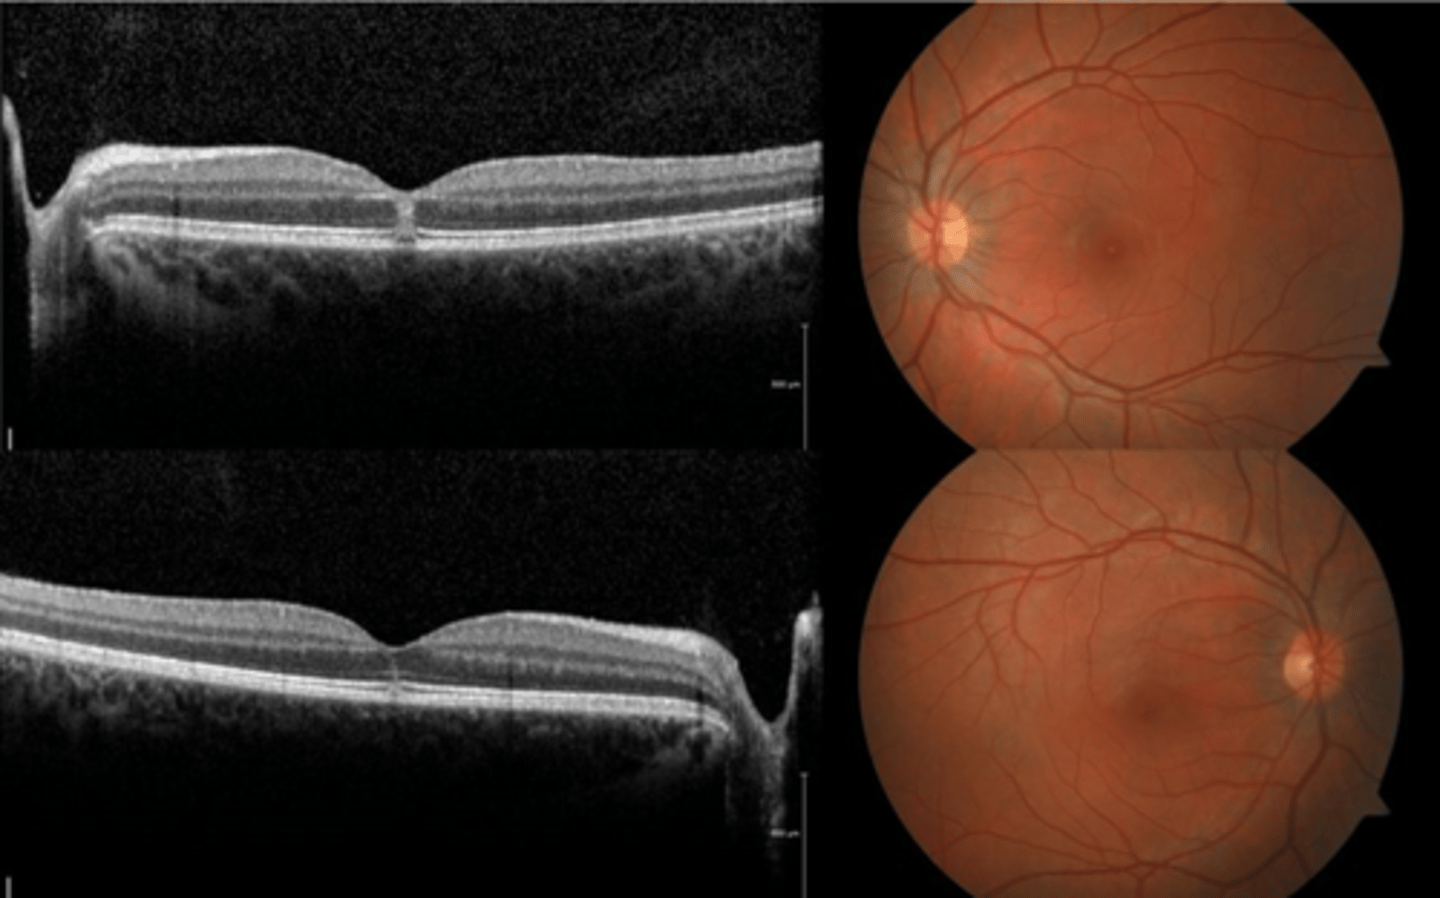

How does choroidal rupture appear on OCT here?

loss of RPE continuity at site of rupture = inner choroid atrophy

How does choroidal rupture appear on OCT here?

RPE disruption

+/- hemorrhage